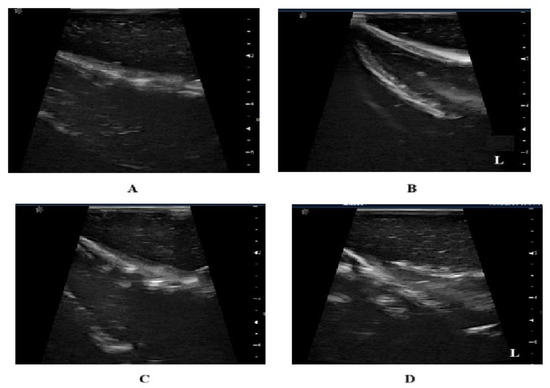

| Technique | Sensitivity | Specificity |

|---|---|---|

| Mammography 1 | 67.8% | 75% |

| Ultrasound 1 | 83% | 34% |

| DOM with 3D image reconstruction | 72% | 68% |